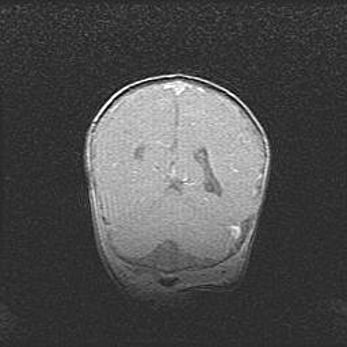

Сообщающаяся гидроцефалия. Кистозная энцефаломаляция головного мозга.

Возраст: 3 месяца 4 дня

Вес: 3100 г

Пол: женский

Окружность головы: 34 см

Срок гестации: 31 неделя

Кистозная энцефаломаляция головного мозга - одна из форм поражения головного мозга в детском возрасте. Характеризуется возникновением множественных и распространённых кист в коре, белом веществе и подкорковых образованиях головного мозга у плодов, новорождённых и детей раннего возраста. Развитие кистозной энцефаломаляции связано с внутриутробной асфиксией и гипотонией, родовой травмой, тромбозом синусов, пороками развития сосудов, инфекциями, сепсисом и другими причинами. Наиболее значимые инфекционные агенты: вирусы простого герпеса, цитомегалии, краснухи, токсоплазмы, энтеробактерии, золотистый стафилококк и другие.